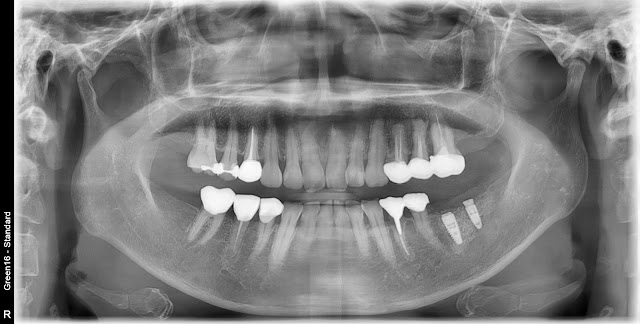

Implant placement in a patient with osteoporosis

A 59-year-old female patient with a history of osteoporosis medication for about 3 years and a drug holiday of approximately 6 months for implant placement. Based on the CT findings, the bone quality of the lower left posterior area appears to be similar to D4 and the bone width also appears narrow.

During the surgery, a radiograph was taken showing that the initial stabilization of the implant in the area of tooth #36 was not successful, causing it to continuously shift downward into the bone. This has made the removal of the implant quite challenging, and there is a risk that it could further embed itself deeper into the bone if not managed carefully.

Subsequently, allograft was transplanted into the bone, and the implant was re-implanted cautiously. Guided bone regeneration (GBR) was also performed on the buccal side.

With no other option, the cortical bone on the buccal side was cautiously removed using a round bar, and the implant was delicately extracted using forceps.

Such symptoms can also occur in the maxillary posterior region, and although rare, they can also be observed in the mandibular posterior region.